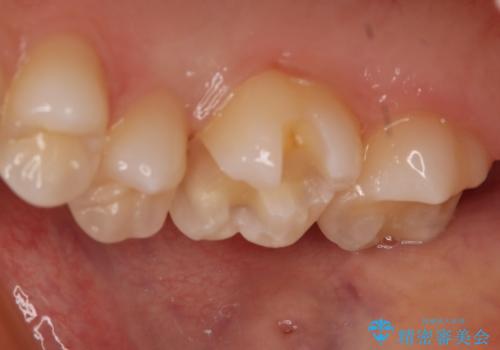

- 右上6番の保険材料で詰められた部分をセラミックにやり変え希望の患者様です。

切削量などを考慮し、セラミックインレーでの治療を選択しました。

- 77000円(税込)費用は治療当時の料金となります

う蝕が深くまで進行していたので、全て除去した上でCR裏層を行い形成、印象を行っています。